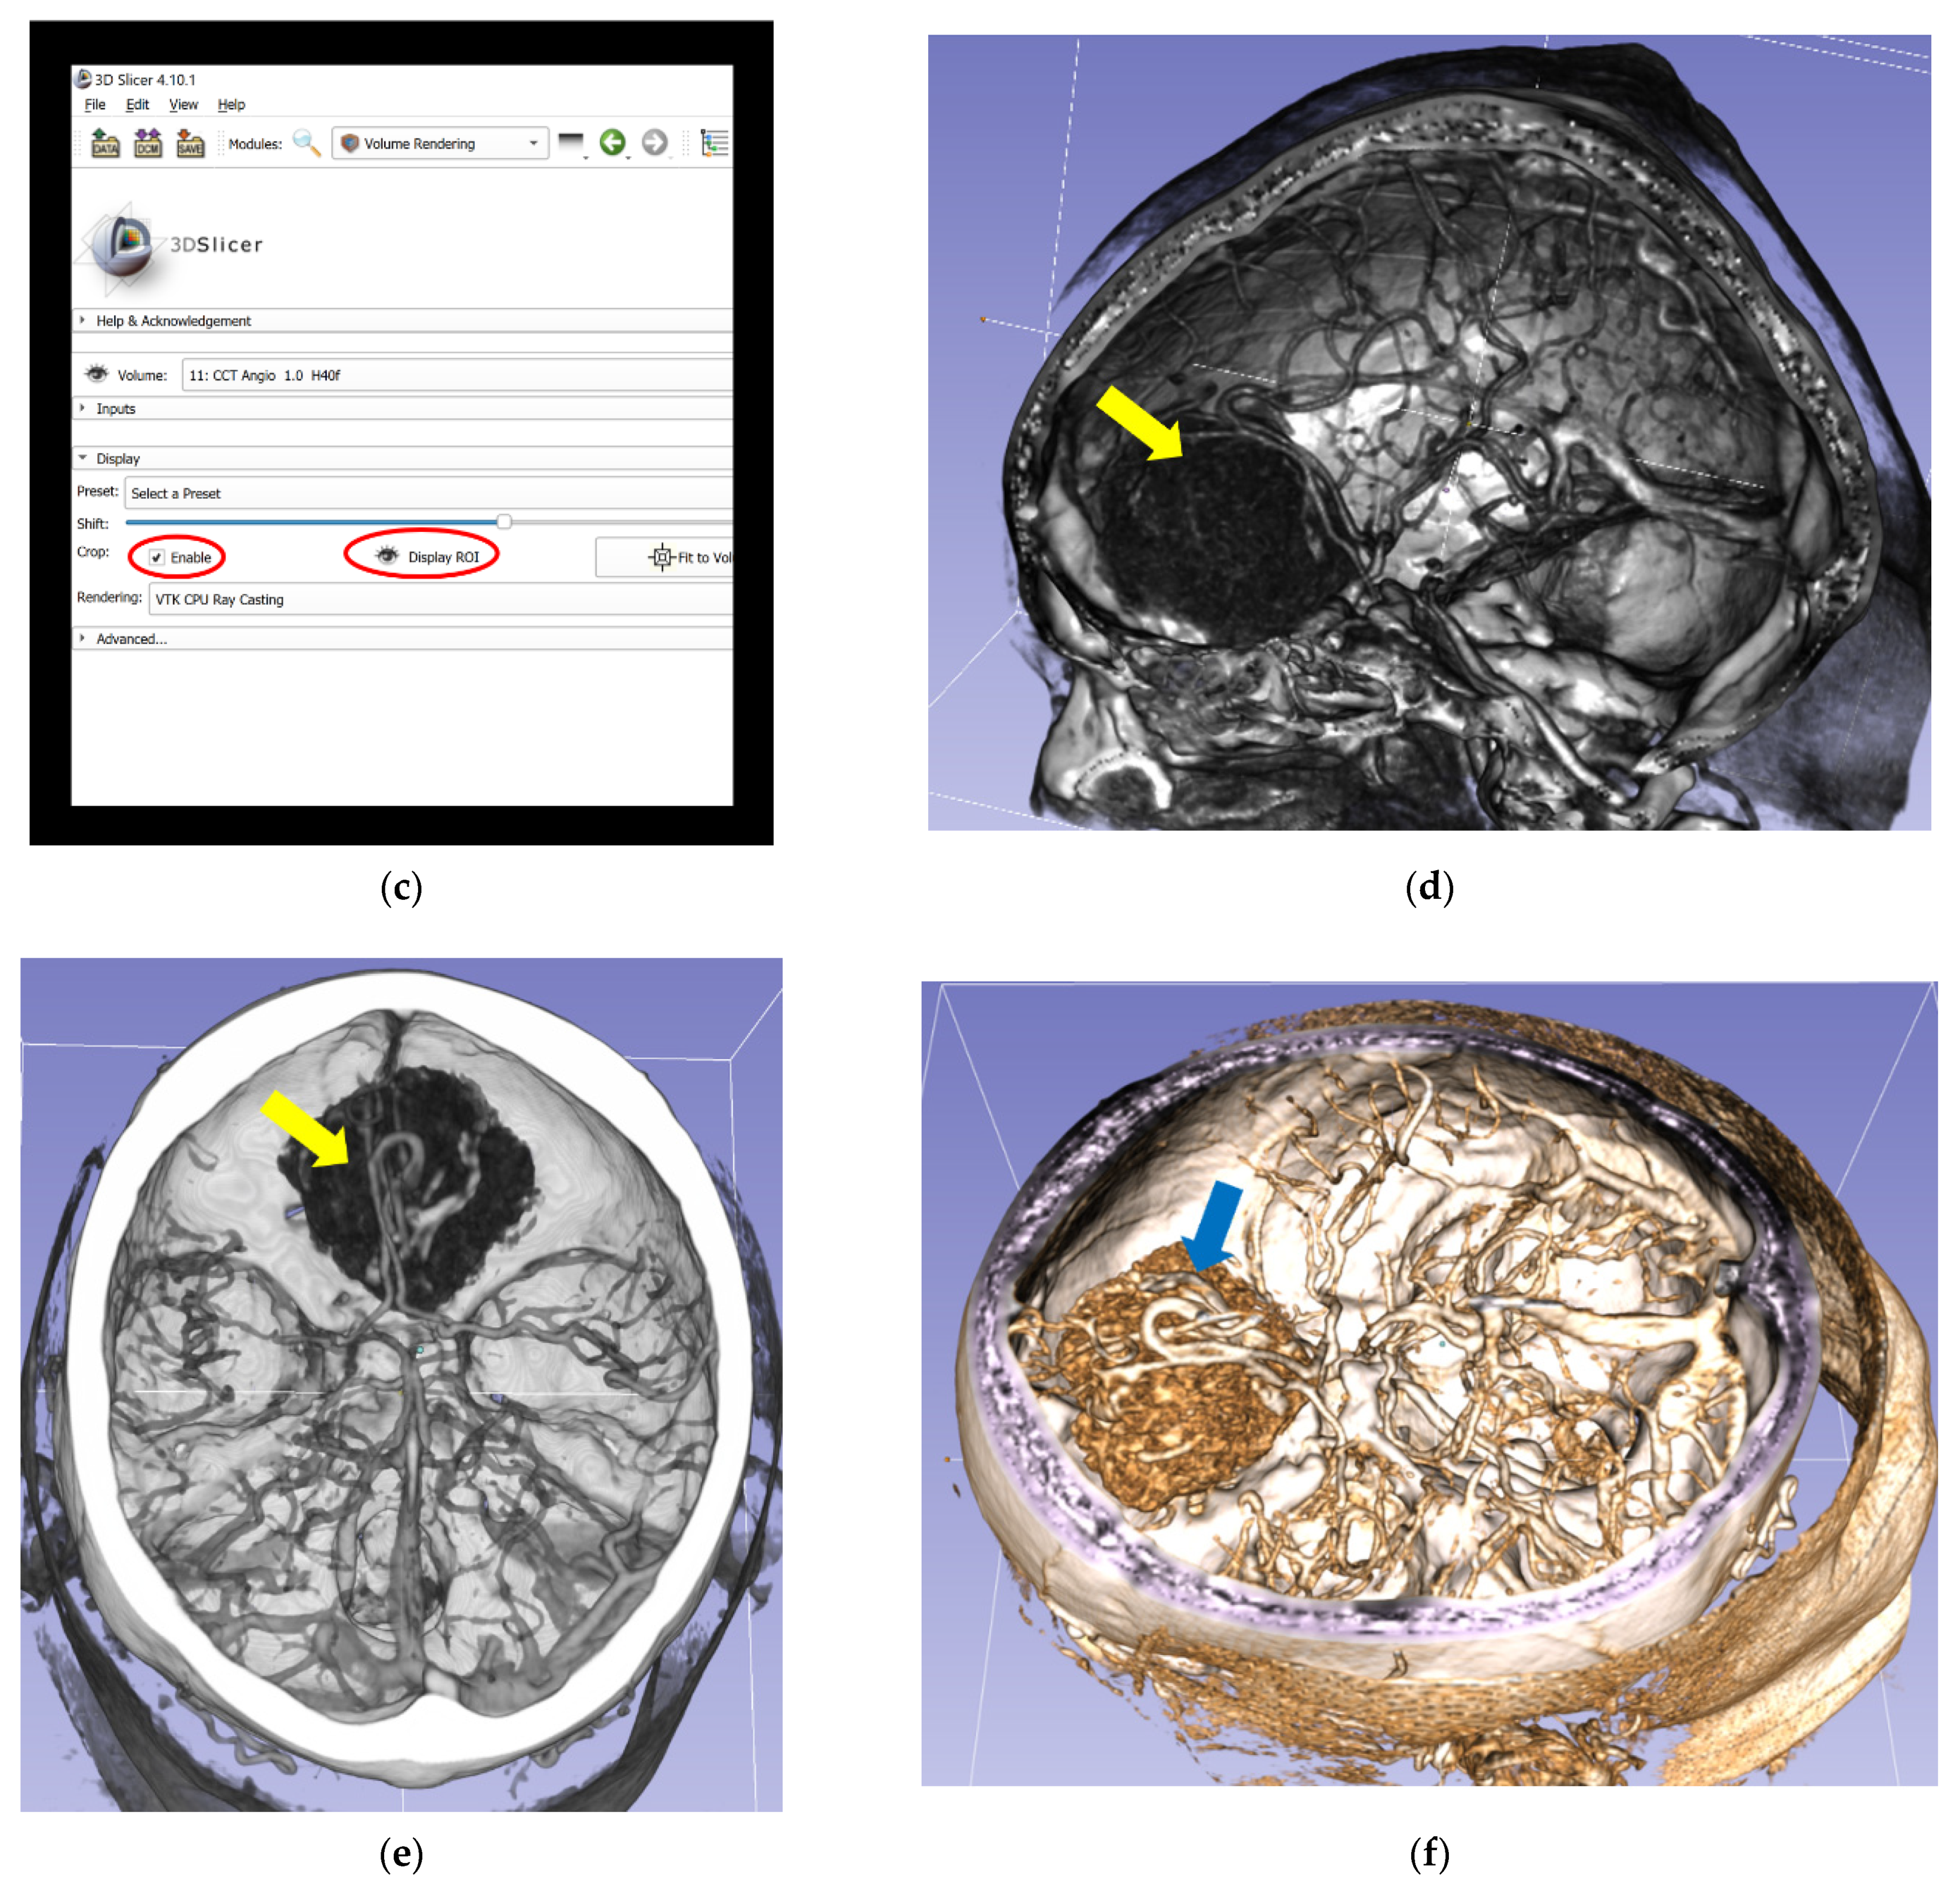

2.4. Virtual Reality Visualization Technique

The digital imaging and communications in medicine (DICOM) files of preoperative 2D-CT and 2D-MRI scans were retrospectively reconstructed to 3D-VR images. We used open-source medical image analysis and visualization software (3D Slicer, Surgical Planning Laboratory, Harvard University, USA) [18], which runs on a VR workstation (main board: Intel Core i7-6800 K (Intel Corporation, Santa Clara, CA, USA); RAM: 16 GB; graphic card: 2 X NVIDIA GTX 1080 (NVIDIA Corporation, Santa Clara, CA, USA)) connected to HTC Vive (HTC Corporation, Xindian District, New Taipei City, Taiwan) goggles, and the SteamVR tracking and controller system (Valve Corporation, Bellevue, WA, USA). The steps of the reconstruction process from 2D-CT modalities, which are the same steps for the reconstruction process from 2D-MRI modalities, are shown in Figure 1. To assess the effectiveness of this method, the duration of the reconstruction process, including completion of the final VR scene, was calculated.

Figure 1. Reconstruction process of 3D-VR images from 2D-CT modalities (including CTA) and completion of the final VR scene in the 3D Slicer. (a) Import of original CT and CTA data in an anonymized DICOM format into 3D Slicer software to create a patient-specific database and selection of “CCT Angio-Default” (blue arrow) in the volume rendering window (red circled). (b) Performance of 3D-VR reconstruction of a skull (yellow arrow) in the volume rendering window. (c) Activation of the ROI function (red circled), which enables visualization of the meningioma and relevant vascular anatomy from different perspectives by partial omission of skull bones. (d) Lateral aspect of the meningioma (yellow arrow) and relevant vascular anatomy, simplified by using the ROI function. (e) Superior aspect of the meningioma (yellow arrow). (f) Superior lateral aspect of the meningioma (blue arrow) with different color displays. 2D, two-dimensional; 3D, three-dimensional; CT, computed tomography; CCT, cranial computed tomography; CTA, computed tomography angiography; DICOM, digital imaging and communications in medicine; ROI, regions of interest; VR, virtual reality.